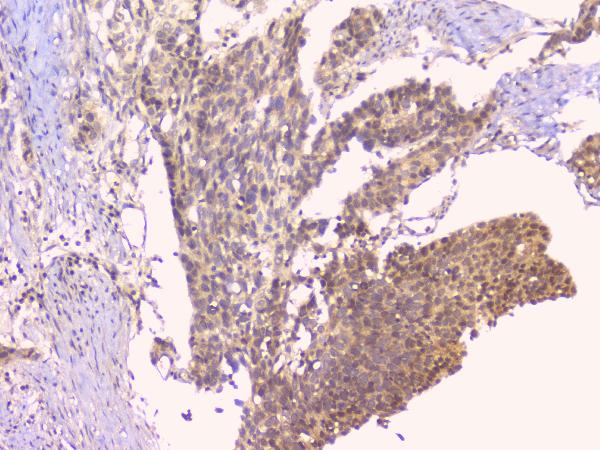

IHC analysis of OPG/TNFRSF11B using anti-OPG/TNFRSF11B antibody (A00863).

OPG/TNFRSF11B was detected in a paraffin-embedded section of human mammary cancer tissue. Biotinylated goat anti-rabbit IgG was used as secondary antibody. The tissue section was incubated with rabbit anti-OPG/TNFRSF11B Antibody (A00863) at a dilution of 1:200 and developed using Strepavidin-Biotin-Complex (SABC) (Catalog # SA1022) with DAB (Catalog # AR1027) as the chromogen.